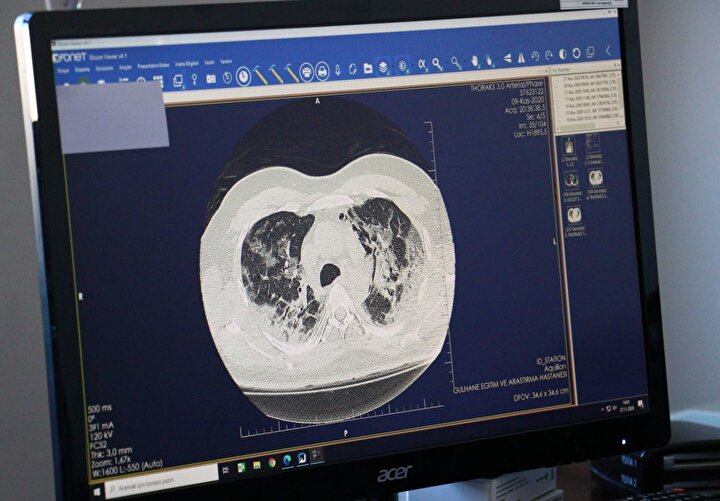

Sağlık Bilimleri Üniversitesi Gülhane Eğitim ve Araştırma Hastanesi'nde Covid-19 tedavisi gören hastaların akciğerlerindeki tahribat, tomografi görüntülerine yansıdı.

Görüntülerde, hastalığın ne kadar hızlı ilerlediği, akciğeri nasıl tuttuğu ve yarattığı hasar gözler önüne serildi.

Göğüs Hastalıkları Uzmanı Doç. Dr. Cantürk Taşçı, Covid-19'un akciğere girişini ve bıraktığı hasarı anlattı.